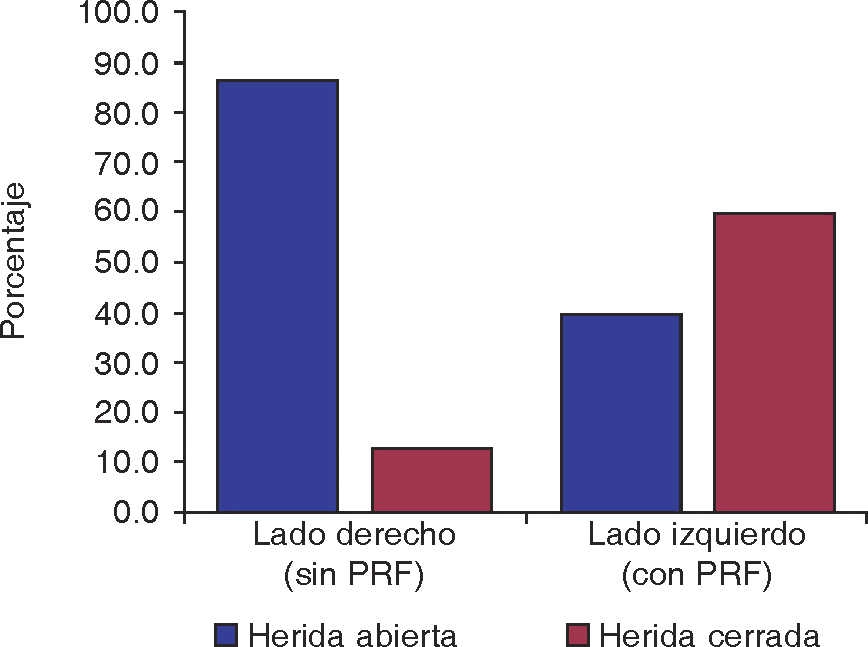

La cicatrización de la herida de tejido gingival se presentó abierta en 26 casos y cerrada en cuatro casos en el lado de control, comparando con 12 heridas abiertas y 18 cerradas en el lado izquierdo en donde fue colocado PRF; teniendo una significancia de p < 0.001 (Figura 6). No se observaron diferencias relacionando por sexo p = 1, tampoco por edad p = 0.49 (Cuadro I).

El uso de PRF en nuestro estudio dio como resultado p < 0.001, lo que nos indica que la cicatrización de tejido blando se ve favorecida con el uso de este compuesto, con base en las estadísticas obtenidas.

El análisis de los resultados de cicatrización de tejido blando por sexo, arroja como resultado p = 1, con lo que se concluyó que el cierre de la herida no depende del sexo del paciente. Del mismo modo procesados los datos por edad, la prueba de χ2 determinó que en el grupo experimental la edad no influye en la cicatrización del tejido blando dando como resultado p = 0.49.